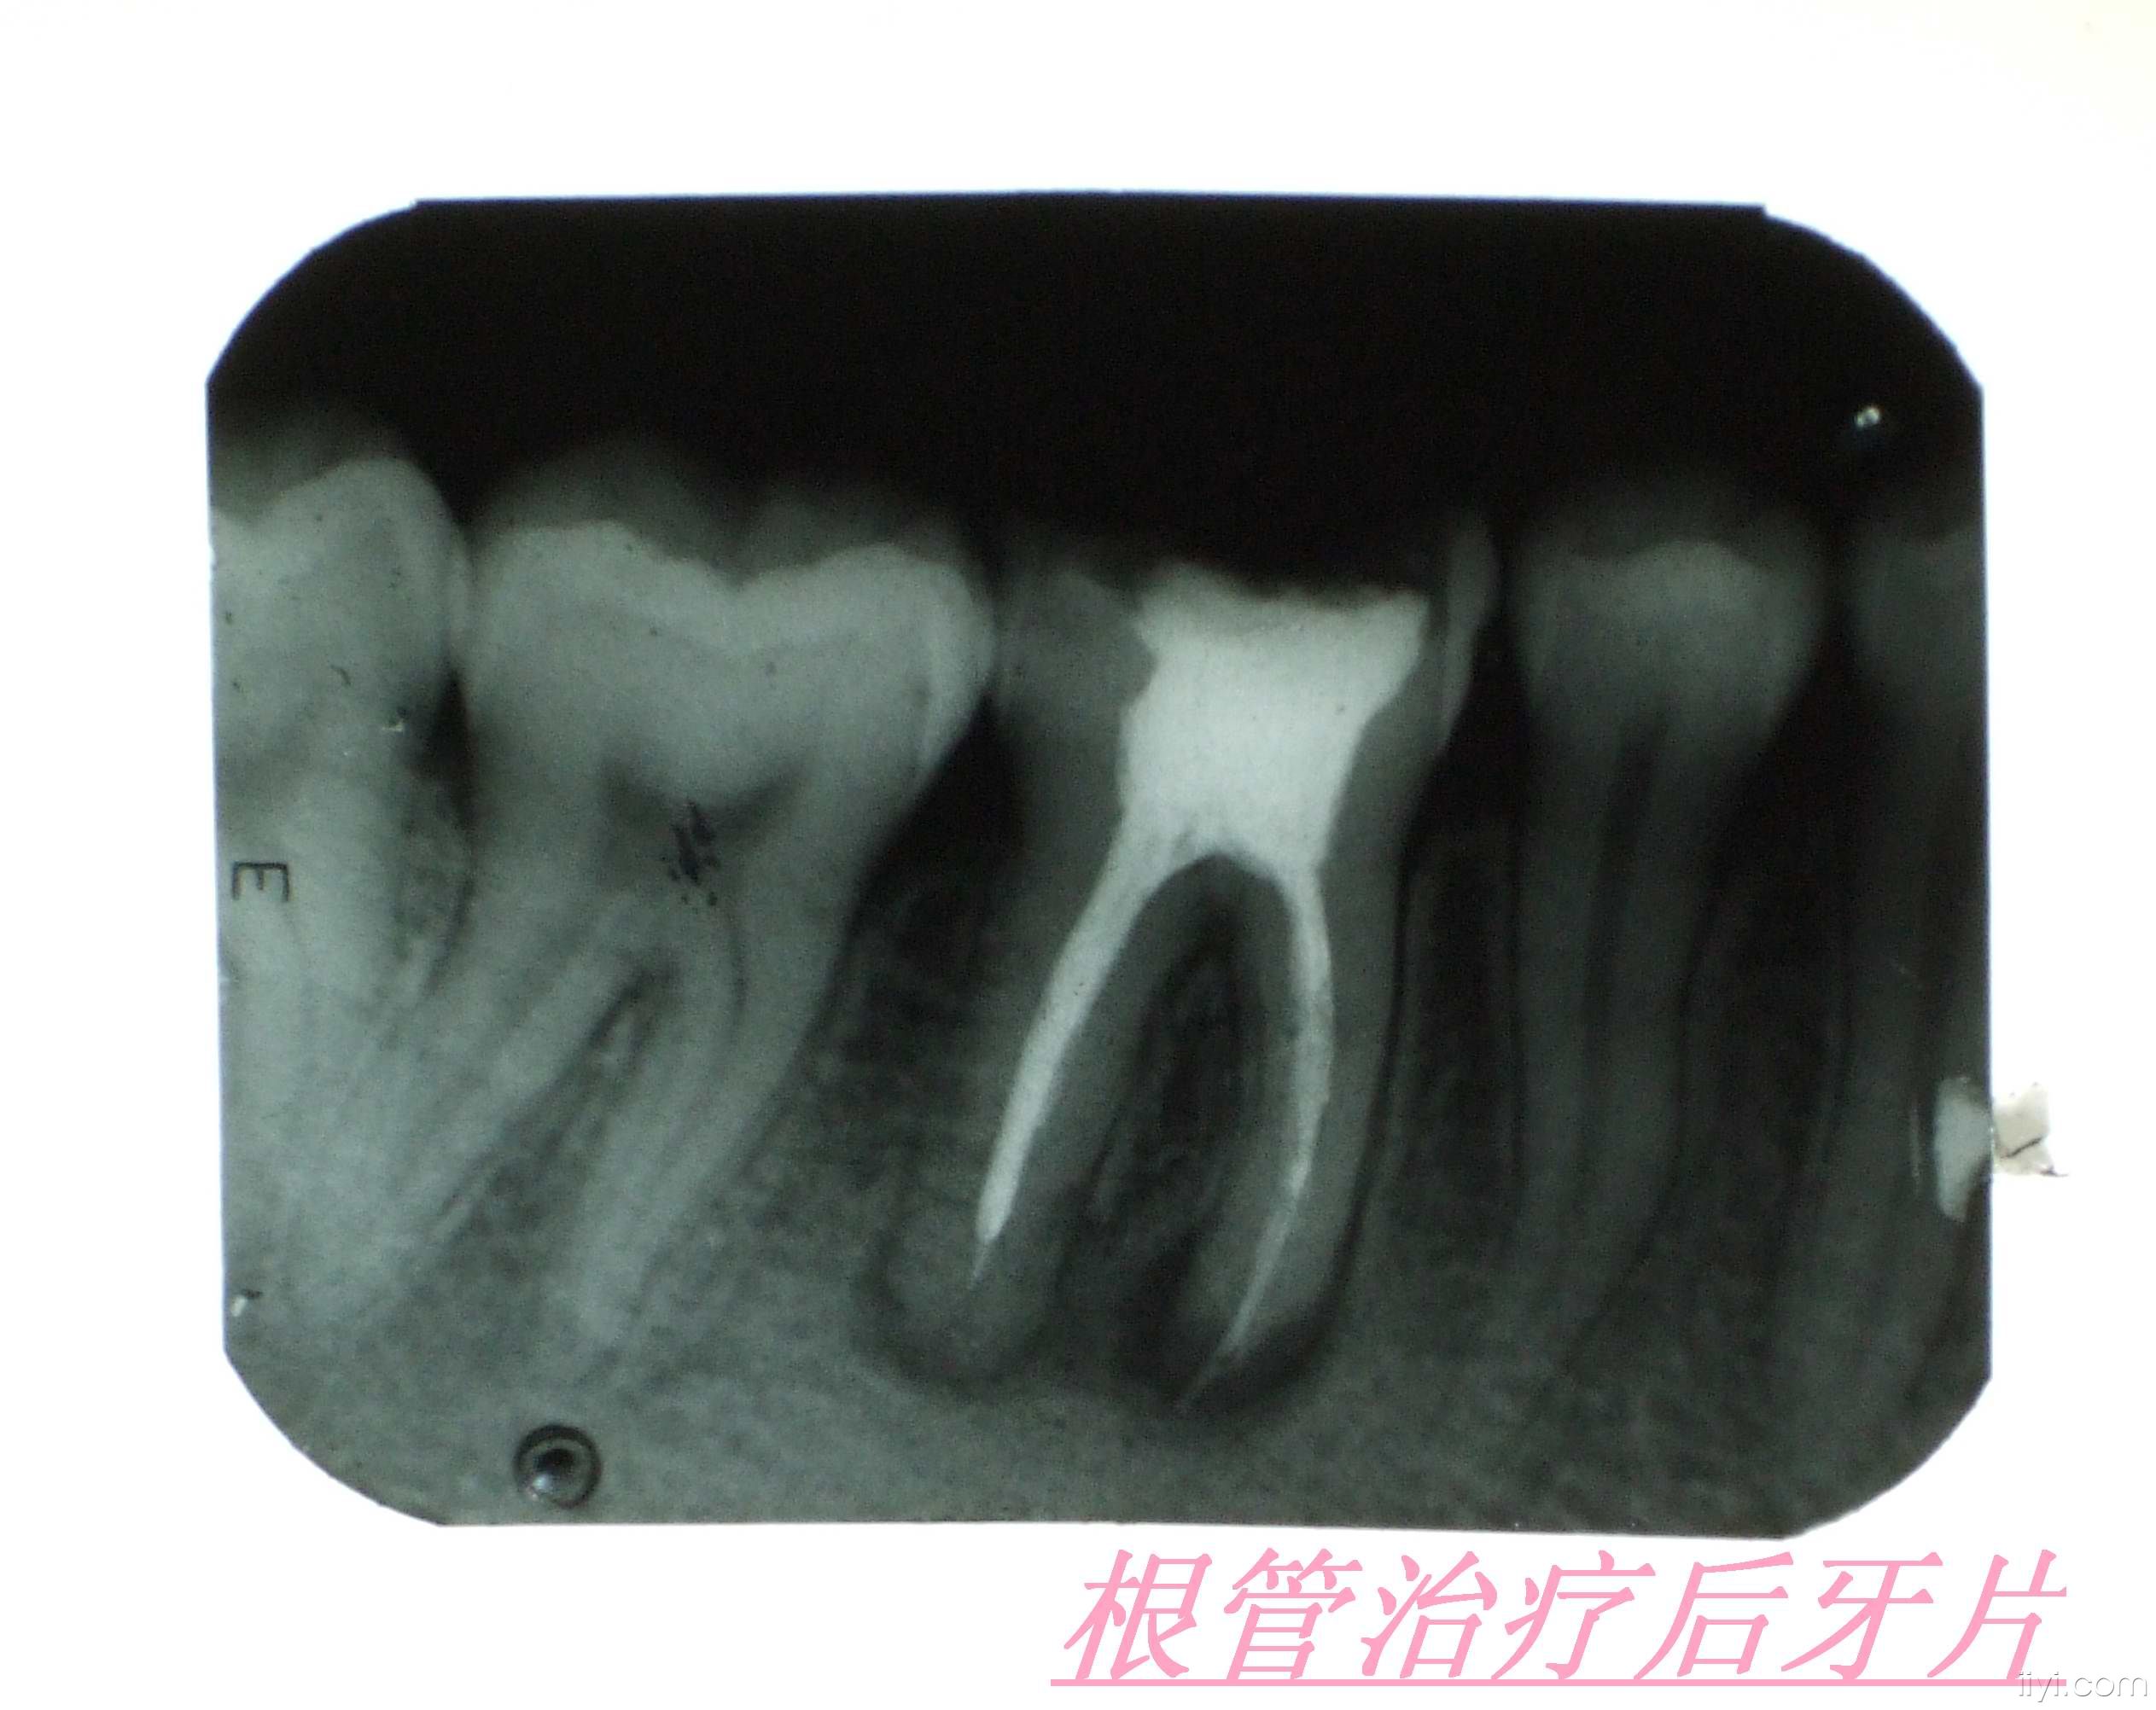

现在很多人都会蛀牙,然后很多人发现蛀牙的时候,往往都是比较严重了,需要进行根管治疗——也就是要截取牙神经。

1、一般根管治疗后都是建议要套一个冠。根管治疗后套冠是为了保护失去活力的牙齿,防止牙齿崩裂。